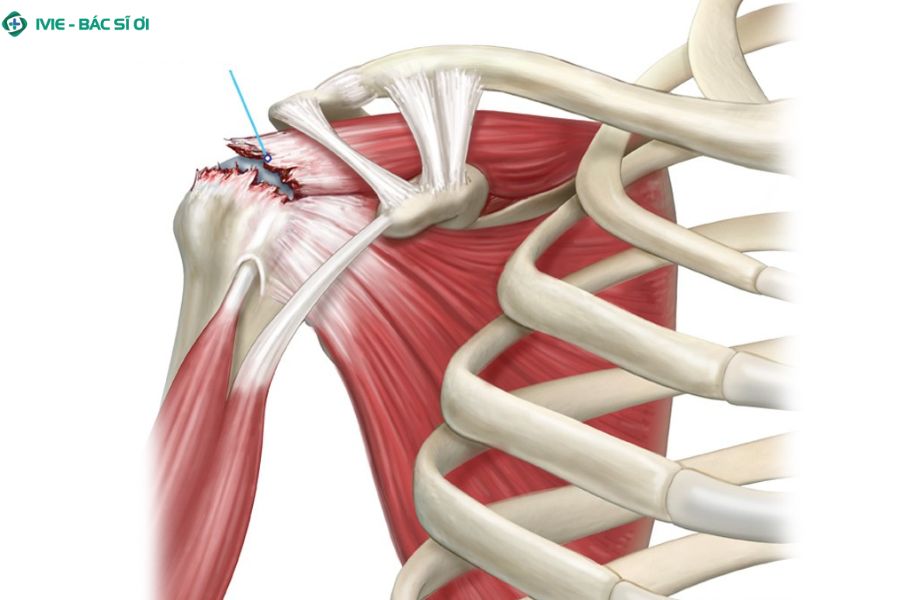

Rách cơ chóp xoay ở vai

Cơ chóp xoay vai tổn thương tại đây có thể gây đau lan lên cổ

Cơ chóp xoay là nhóm cơ giúp vai cử động linh hoạt. Khi nhóm cơ này bị rách (một phần hoặc toàn bộ), người bệnh sẽ cảm thấy đau ở vùng vai ngoài, đặc biệt nếu tổn thương xảy ra ở bên trái. Cơn đau có thể lan lên cổ hoặc xuống cánh tay cùng bên, kèm theo cảm giác vai yếu, phát ra tiếng lạo xạo khi cử động hoặc đau khi nâng tay. Đây là một trong những nguyên nhân thường gặp gây đau cổ vai gáy bên trái.